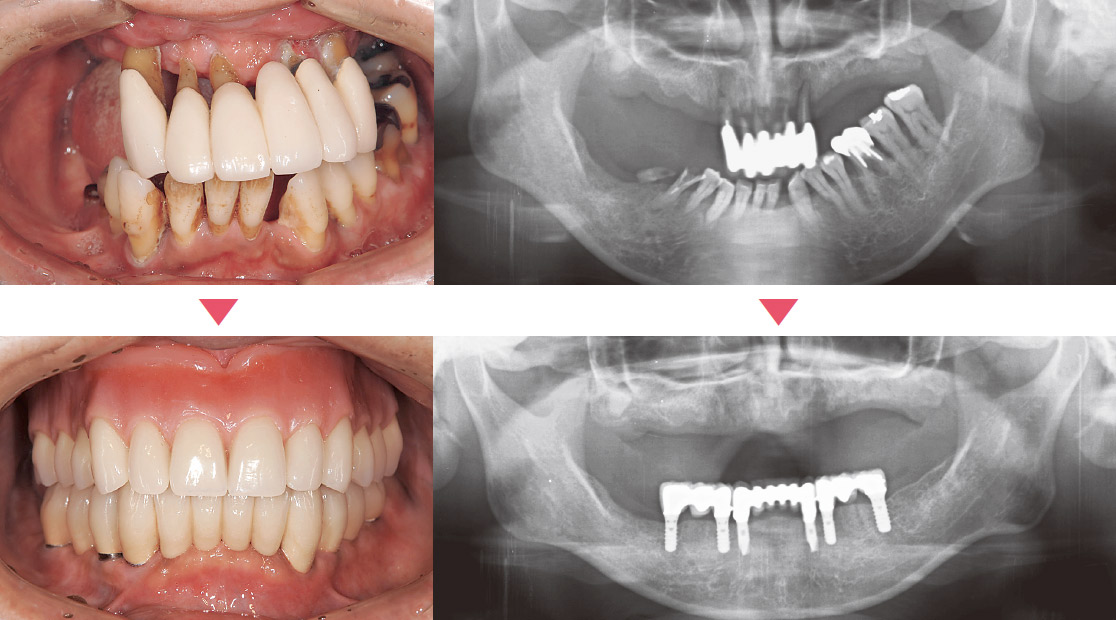

18本の歯が存在するがほとんど噛めない状況である。下顎に6本のインプラントを用い、上顎は総義歯とした。

天然歯は1本も存在しないが咀嚼が充分できる状況となった。